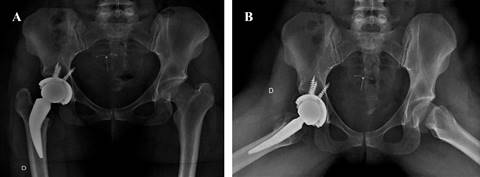

A todos los pacientes se les implantó una copa acetabular no cementada JUMP Traser® System (Permedica, Italia) y un vástago Alteon Neck Preserving® (Exactech, Estados Unidos), con un par de fricción metal-polietileno. Se realizó tromboprofilaxis con enoxaparina 40 mg cada 24 horas. El mismo día de la cirugía, se indicaron ejercicios de contracción del cuádriceps, sedestación y bipedestación. En los días siguientes, se brindó educación sobre la marcha con andador y se progresó gradualmente en la carga de peso según la tolerancia del paciente.

Evaluación radiográfica

La anteversión acetabular tuvo un promedio de 10o (IQR 0o-15o), no observándose componentes acetabulares retroversos. El ángulo de inclinación tuvo una mediana de 43o (rango intercuartílico [RIC]: 38o a 51o). En dos (9.9%) pacientes se detectaron líneas radiolúcidas sin progresión o significancia clínica; el resto de los sujetos presentaron cinco de los signos radiográficos de Moore para osteointegración del cotilo. En 20 pacientes (90.1% de la serie), la medición postoperatoria de la longitud de los miembros no encontró discrepancia entre el operado y el contralateral, en un caso se presentó una hipermetría menor a 0.5 cm y una hipermetría entre 0.5 a 1 cm. En ningún caso hubo disconformidad con el resultado funcional. Se detectó la aparición de calcificaciones heterotópicas de tipo 1 (clasificación de Brooker) en dos casos, sin ninguna relevancia clínica.

Acetábulo. El componente acetabular utilizado es de titanio trabecular con impresión 3D por EBM (Electron Beam Molding), con un coeficiente de fricción alto y una porosidad aumentada. Estas propiedades, según lo analizado por Saleh, reducen el micromovimiento, mejorando la estabilidad y la fijación inicial, además de favorecer la osteointegración.18 Los resultados obtenidos muestran una fijación estable sin alteraciones durante el período de seguimiento promedio de 40.7 meses, con líneas radiológicas de osteointegración, de acuerdo con los criterios de Moore. Estos hallazgos coinciden con lo reportado en cotilos de fabricación similar, como describe Geng. En su estudio, no hubo fallas en 92 casos, con la aparición de líneas radiolúcidas en 18 caderas, líneas que desaparecieron en seis meses, y una tasa de supervivencia general de 99.1%, con una tasa de supervivencia del cotilo de 100%.19

Con respecto a la orientación de los cotilos, todos se encontraron dentro de la zona de Lewinnek, con un promedio de 43o y una anteversión promedio de 10o. Resultados equivalentes a los logrados en series con implantes similares en población joven.23,24

Vástago. La filosofía de fijación del vástago investigado, catalogado como tipo 1B según la clasificación de Kheir, se basa en una fijación en tres puntos: calcar, cortical proximal femoral y metáfisis. Esto proporciona estabilidad rotacional sin invadir el canal diafisario, lo que evita parte de las incongruencias que se observan en los fémures tipo A (según la clasificación de Dorr), más frecuentes en adultos jóvenes y en secuelas de Perthes y DDC.25,26

La evaluación radiográfica mostró la formación de hueso trabecular alrededor del vástago dentro de los primeros tres a seis meses. Durante el seguimiento, no se observó progresión en los casos de migración inicial. En correlación con los resultados clínicos, coincidimos con estudios previos publicados en un estudio multicéntrico y con los hallazgos de Wittenberg, quienes informaron que estos tallos se estabilizan secundariamente. Jahnke reportó migraciones de hasta 1.5 mm en la orientación en varo-valgo, con posterior estabilización y sin relevancia clínica en pacientes evaluados con Ein Bild Röntgen Analyse (EBRA-FCA). Esto respalda la teoría de que un tallo corto colocado en varo o valgo no necesariamente está mal colocado. Por el contrario, creemos que la versatilidad del vástago de preservación en mayor o menor valgo es una herramienta eficaz para restituir la biomecánica de la cadera nativa del paciente.23,27,28,29